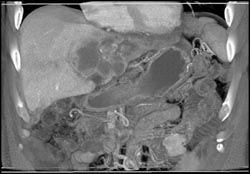

Cholangiocarcinoma